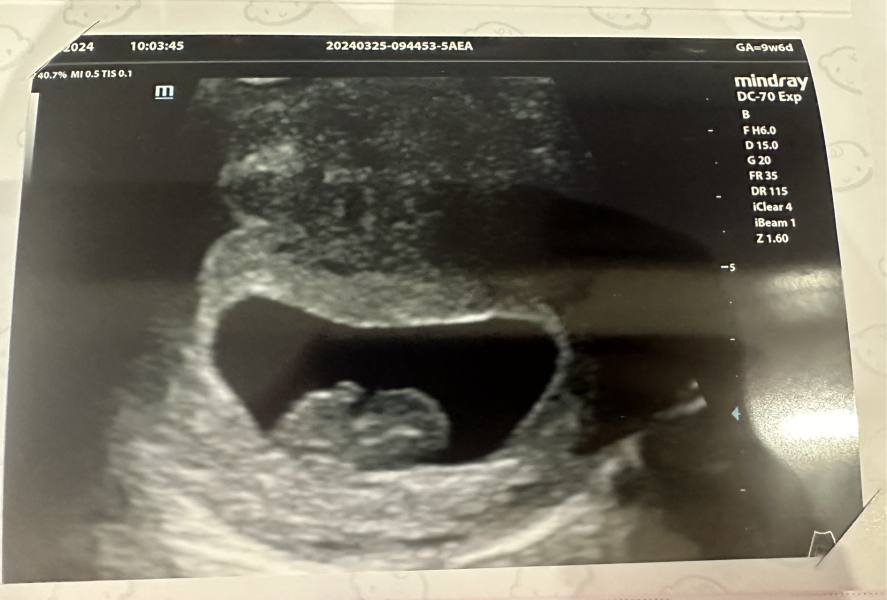

We saw baby this morning - still measuring a week behind but growing exactly as should have done since the last scan :) the hematoma is still there and also growing but they were pretty optimistic it wont impact the pregnancy.